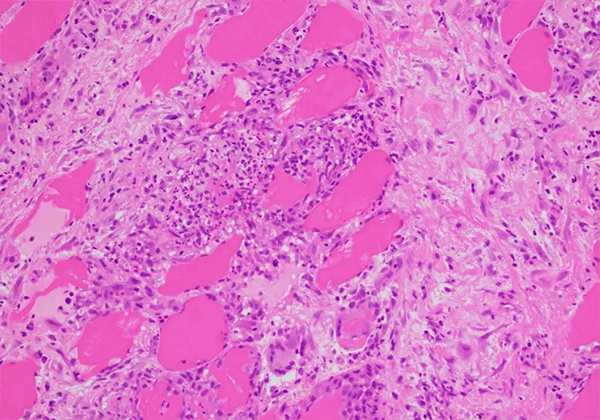

结节病是一种病因不明的慢性多系统炎性疾����。卣魑歉衫已掀ぱ庋恐����,伴有单个核细胞浸润和微结构破坏����。该病可累及皮肤,眼睛����,心脏和中枢神经系统���,超过90%的病例累及肺部����。该疾病是重大的、未满足的医疗需求之一���。